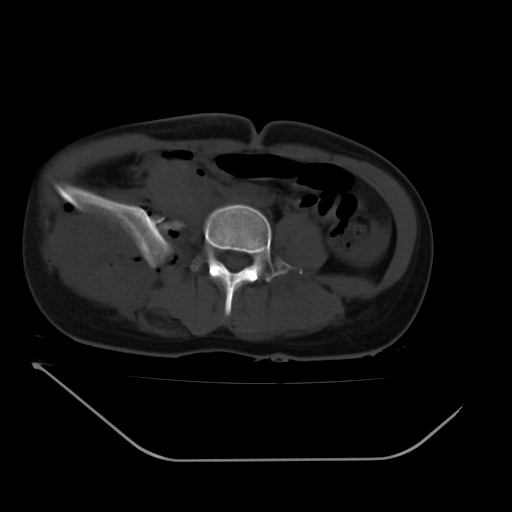

以下是引用liuyue在2008-7-19 13:02:00的发言:[br]1.肝右叶后下段及右肾挫裂伤伴腹腔积血。[br]2.右侧多发性肋骨骨折、横突骨折、右髂骨骨折伴周围软组织挫伤。[br]3.右侧腰大肌肿胀,并可见低密度影,如为气体,则肠道挫裂伤待除外。

以下是引用zhengfaming在2008-7-19 14:42:00的发言:[br]1.肝右叶后下段及右肾挫裂伤伴腹腔积血。脾脏挫裂伤待排[br]2.右侧多发性肋骨骨折、横突骨折、右髂骨骨折伴周围软组织挫伤。[br]3.右侧腰大肌肿胀,并可见低密度影,如为气体,则肠道挫裂伤待除外

以下是引用道哥在2008-7-19 16:52:00的发言:[br]肝右叶后下段及右肾挫裂伤、脾破裂伴腹腔积血。[br]2.双侧多发性肋骨骨折、横突骨折、右髂骨骨折伴周围软组织挫伤。[br]3.右侧腰大肌肿胀,并可见低密度影,如为气体,则肠道挫裂伤待除外。